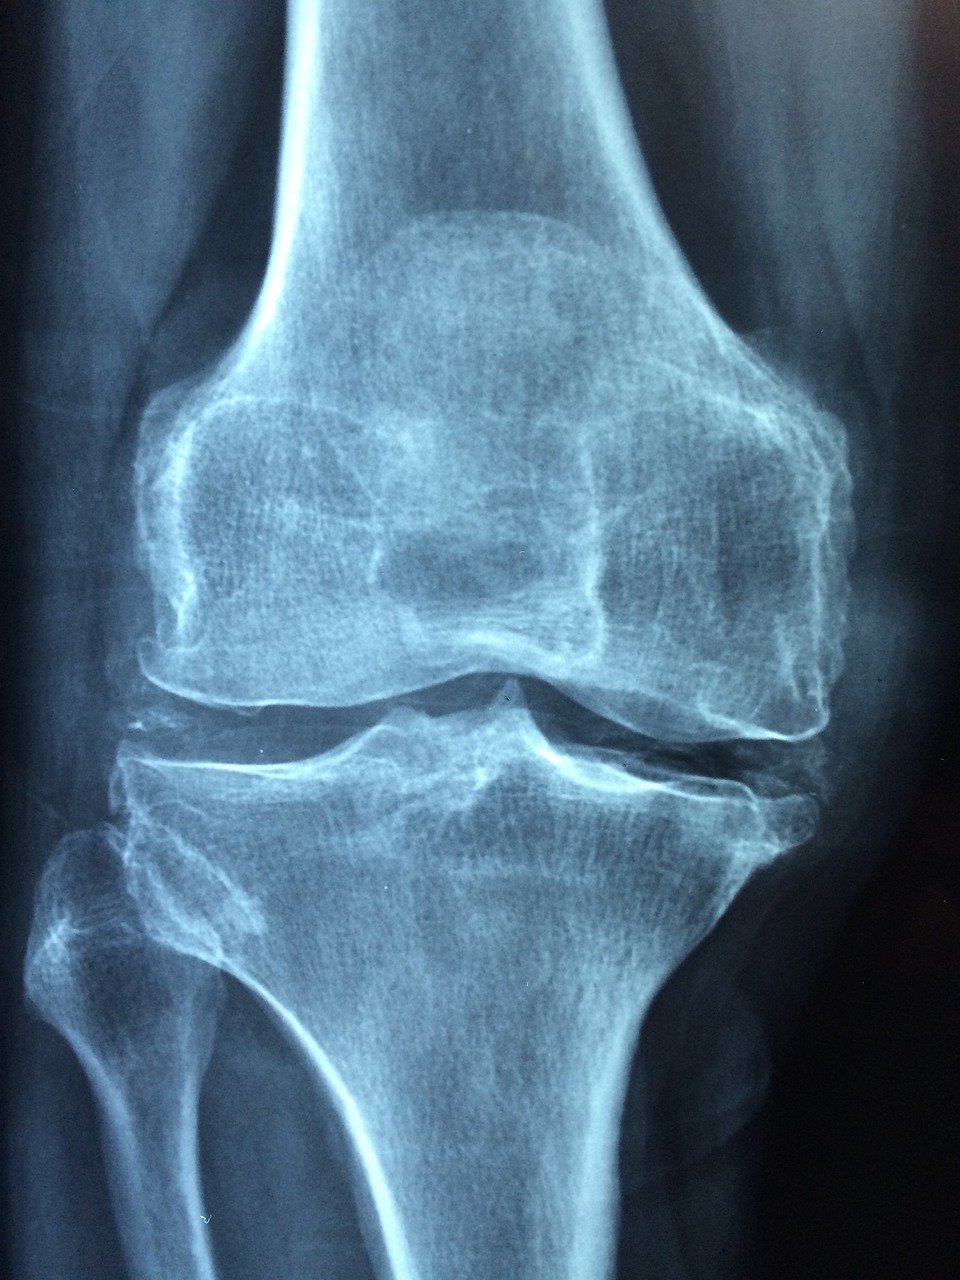

노화가 진행되면 관절 연골 내 세포(연골세포, chondrocyte)의 활동성이 떨어지고, 콜라겐 섬유가 단단해지며 탄력을 잃습니다. 동시에 연골 내 수분 함량이 줄어들어 쉽게 마모되고, 미세한 균열이 생기며 기능 저하가 가속화됩니다. 이는 관절의 운동 범위 감소, 통증, 뻣뻣함 등을 유발하며, 결국에는 퇴행성 관절염(osteoarthritis)으로 진행될 수 있습니다.

활액도 나이가 들수록 점성이 떨어지고 윤활 기능이 저하됩니다. 이는 관절 운동 시 마찰을 증가시키고, 연골의 손상을 더욱 심화시킵니다. 노화에 따른 이러한 변화는 주로 체중 부하가 큰 무릎, 고관절, 발목에서 먼저 나타나며, 특히 여성의 경우 폐경 이후 호르몬 변화로 인해 관절 내 염증 반응이 증가해 골관절염 위험이 높아집니다.

중요한 점은, 관절 손상이 서서히 진행되므로 본인은 초기 징후를 감지하지 못한 채 운동을 계속할 가능성이 높다는 것입니다. 결국 통증이나 부종이 뚜렷해진 후 병원을 찾게 되며, 이 시점에는 이미 연골 손상이 상당 부분 진행된 경우가 많습니다.

2022년 서울대병원 스포츠의학센터에서는 40세 이상 마라톤 참가자 120명을 2년간 추적한 연구를 통해, 주당 러닝 거리가 30km 이하인 경우에는 관절 퇴행이 거의 없거나 오히려 연골의 내구성이 개선되는 경향이 있다는 결과를 발표했습니다. 반면, 주당 60km 이상을 달리며 휴식일 없이 운동을 지속한 그룹에서는 관절 연골의 퇴화 소견이 관찰되었으며, 특히 무릎 내측 연골이 얇아지는 경향이 뚜렷했습니다.